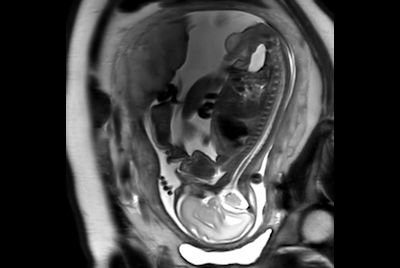

Pediatric pelvis with fistula

Fetal Brain and Spine